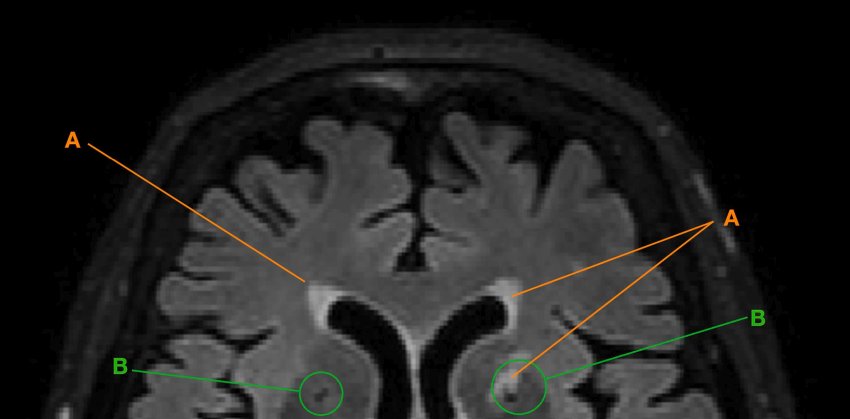

Sezione di cervello nella scansione MR, con iperintensità della materia bianca (A) e lacune (B). Fonte: UZH

Nella sua tesi di dottorato, la prima autrice Isabel Hotz ha usato nuovi metodi automatici, tra gli altri, per studiare le cosiddette lacune e iperintensità della materia bianca. Questi processi degenerativi si presentano come 'buchi neri' e 'punti bianchi' sulle immagini digitali.

Le ragioni di questo fenomeno non sono ancora conosciute e potrebbero aver a che fare con infarti cerebrali, piccoli e inosservati, con flusso sanguigno ridotto o con perdita di percorsi nervosi o neuroni. Ciò può limitare le prestazioni cognitive di una persona, in particolare quando la degenerazione influisce su regioni cruciali del cervello.